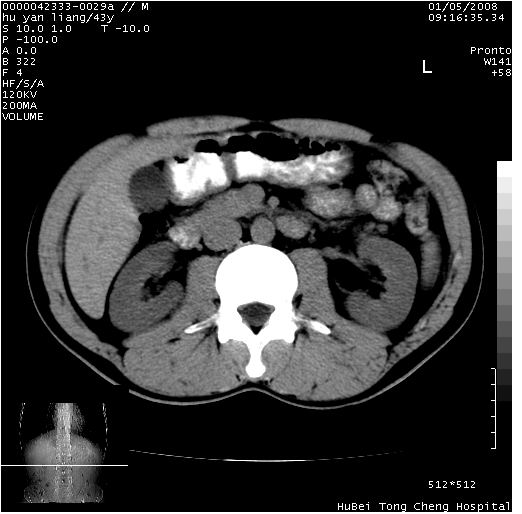

患者 男,43岁。右上腹不适1年余。既往有“肝右叶肝脓肿”病史,经保守治疗后痊愈。

b超提示:1)肝右叶肝内胆管结石。2)肝右叶占位性病变待排。

上中腹部ct轴位平扫+增强扫描(层厚10mm,螺距1.0,重建间隔10mm),图像如下:

肝右上叶偏后方较大团片状钙化灶,支持:肝脓肿后遗改变!

肝右叶后段团块状钙化灶,结合病史考虑肝脓肿痊愈后表现。